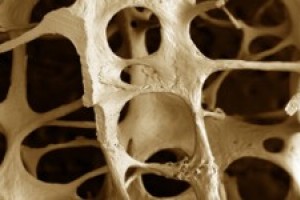

Droga para osteoporose só funciona por cinco anos

09/09/2011

"Mulheres que tomam bisfosfonatos para tratar osteoporose podem interromper o...

Droga para osteoporose só funciona por cinco anos

09/09/2011"Mulheres que tomam bisfosfonatos para tratar osteoporose podem interromper o...